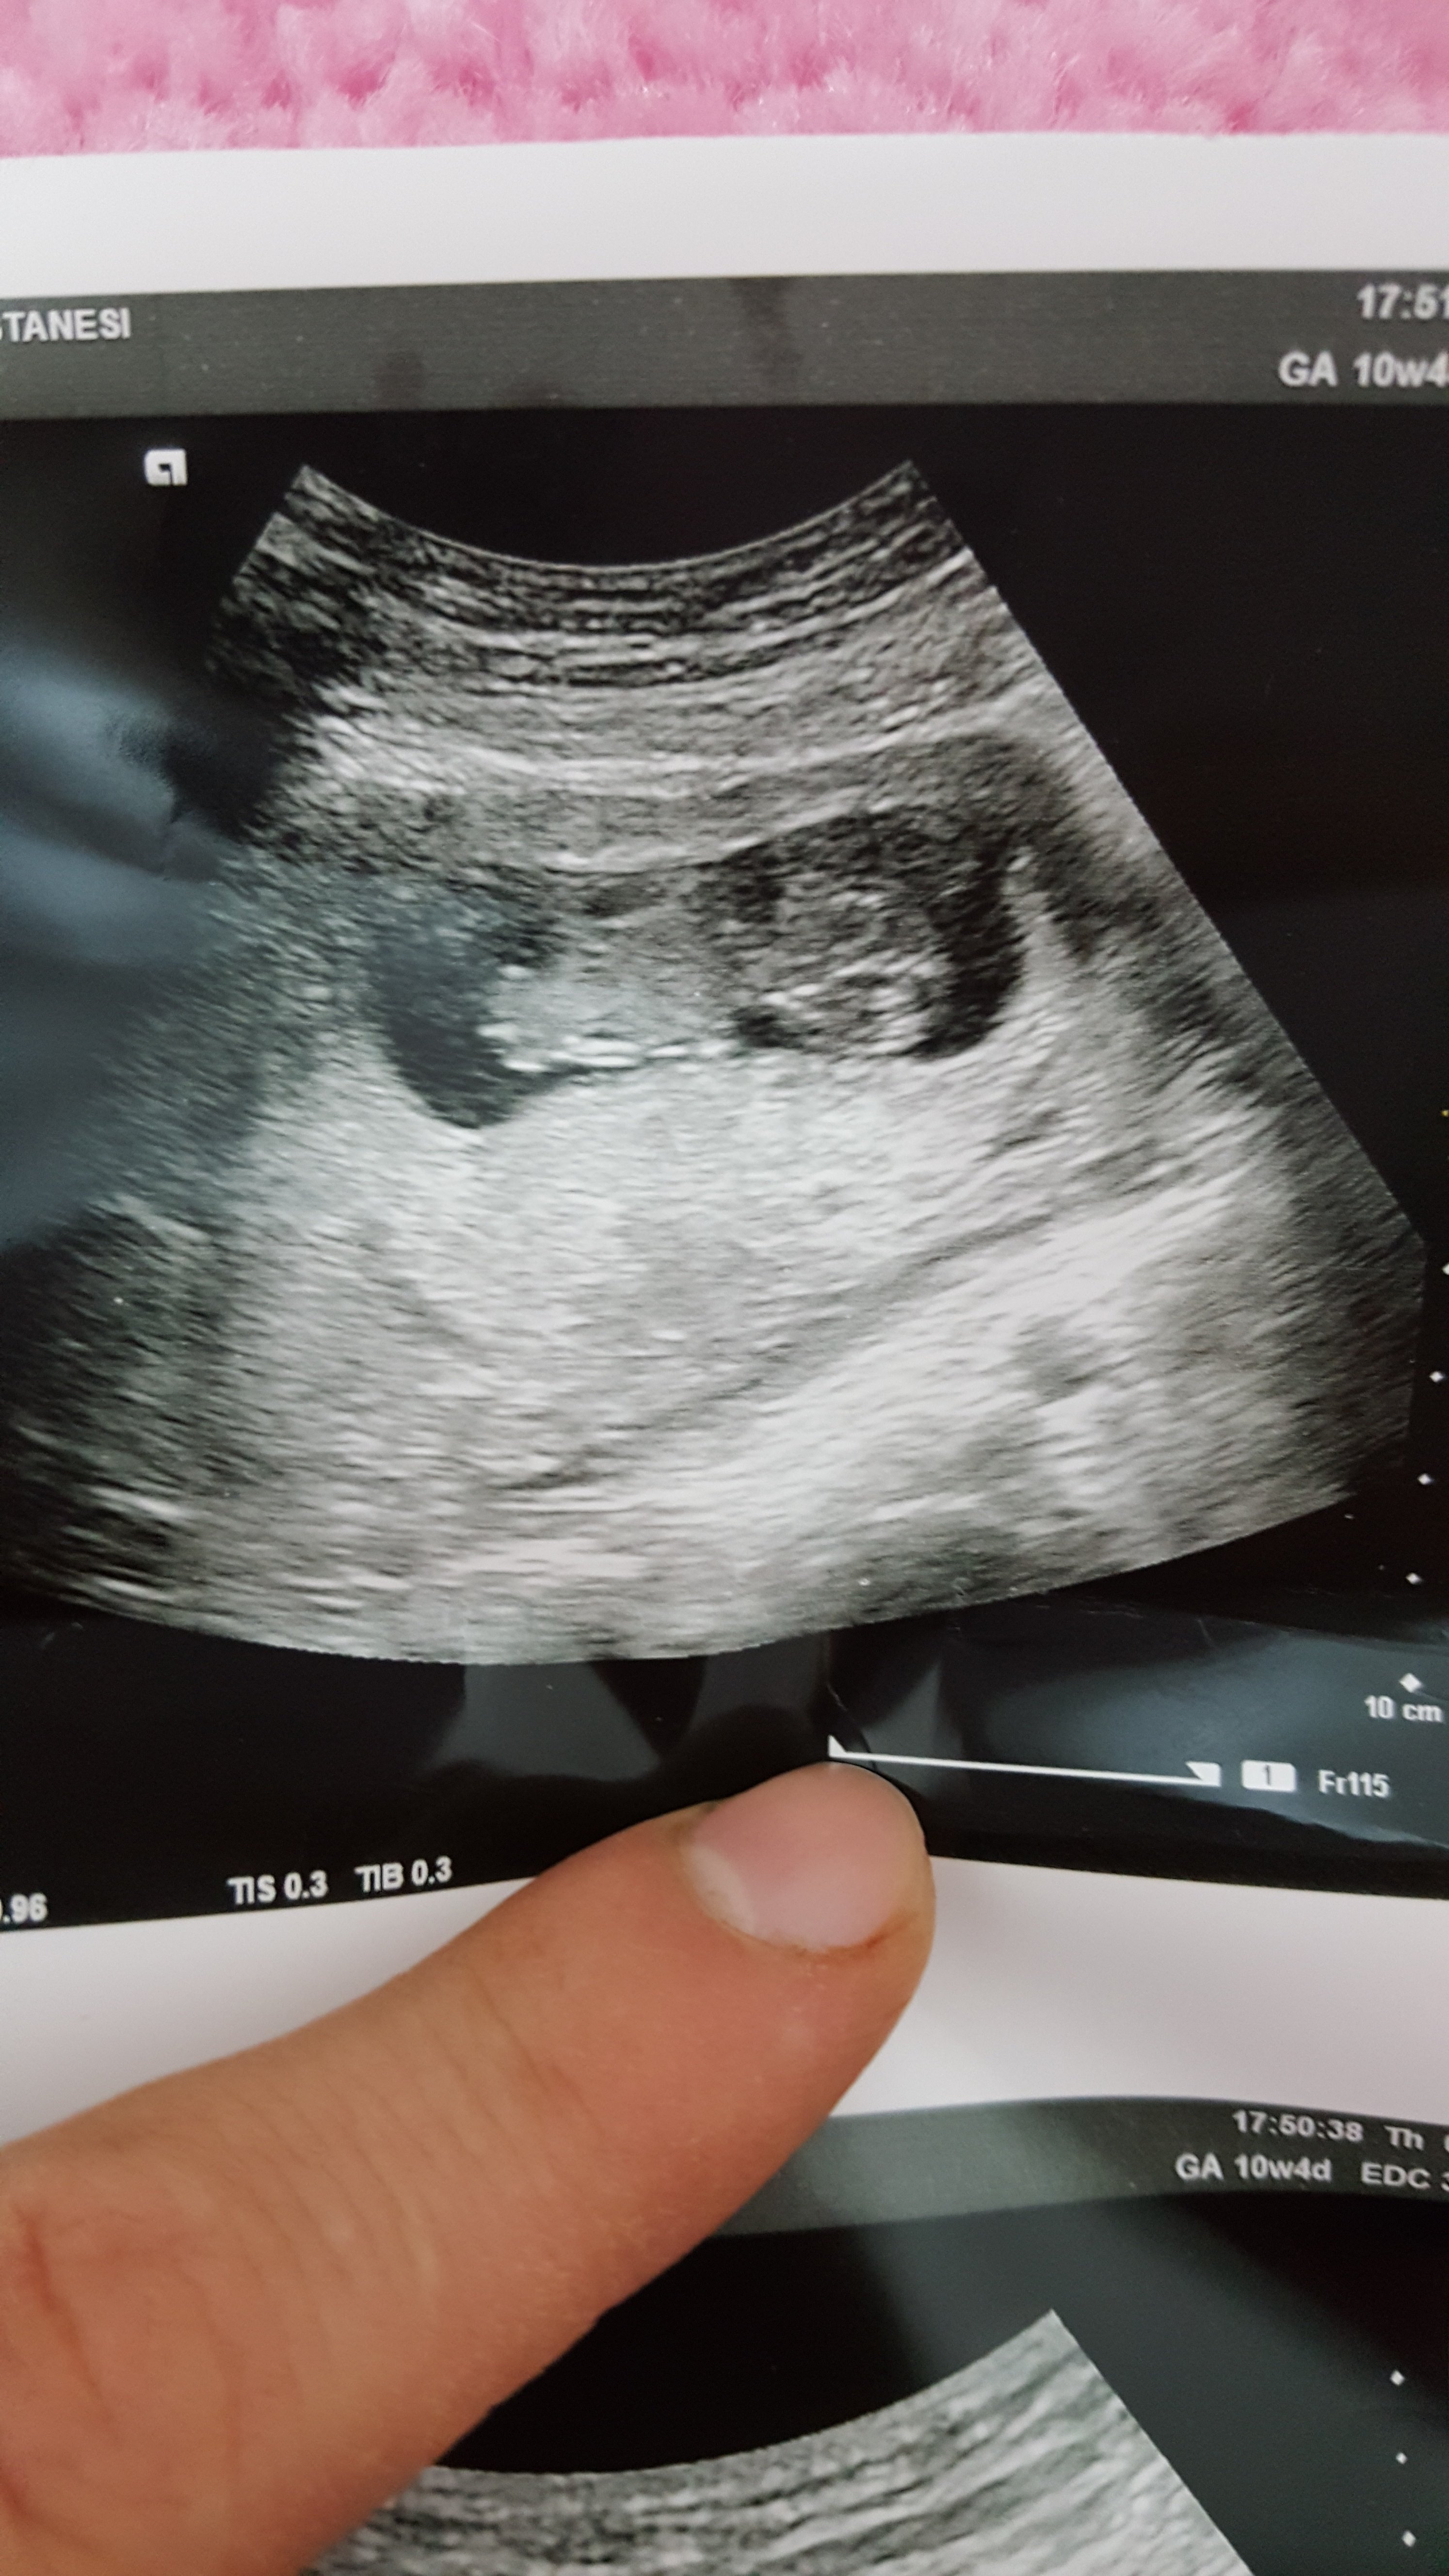

S Sedatunc Yeni Üye Üye 7 Ocak 2017 #118 Lutfenn benimkine de bakar misiniz. Simdiden tesekkur ederim Moderatör tarafında düzenlendi: 8 Ocak 2017

Sevimli cadı Daimi Üye Üye 8 Ocak 2017 #119 Sedatunc' Alıntı: Lutfenn benimkine de bakar misiniz. Simdiden tesekkur ederim Ekli dosyayı görüntüle 73279 Ekli dosyayı görüntüle 73280 Genişletmek için tıkla ... Sizin resimler net değil yorumlayamam malesef

Sedatunc' Alıntı: Lutfenn benimkine de bakar misiniz. Simdiden tesekkur ederim Ekli dosyayı görüntüle 73279 Ekli dosyayı görüntüle 73280 Genişletmek için tıkla ... Sizin resimler net değil yorumlayamam malesef